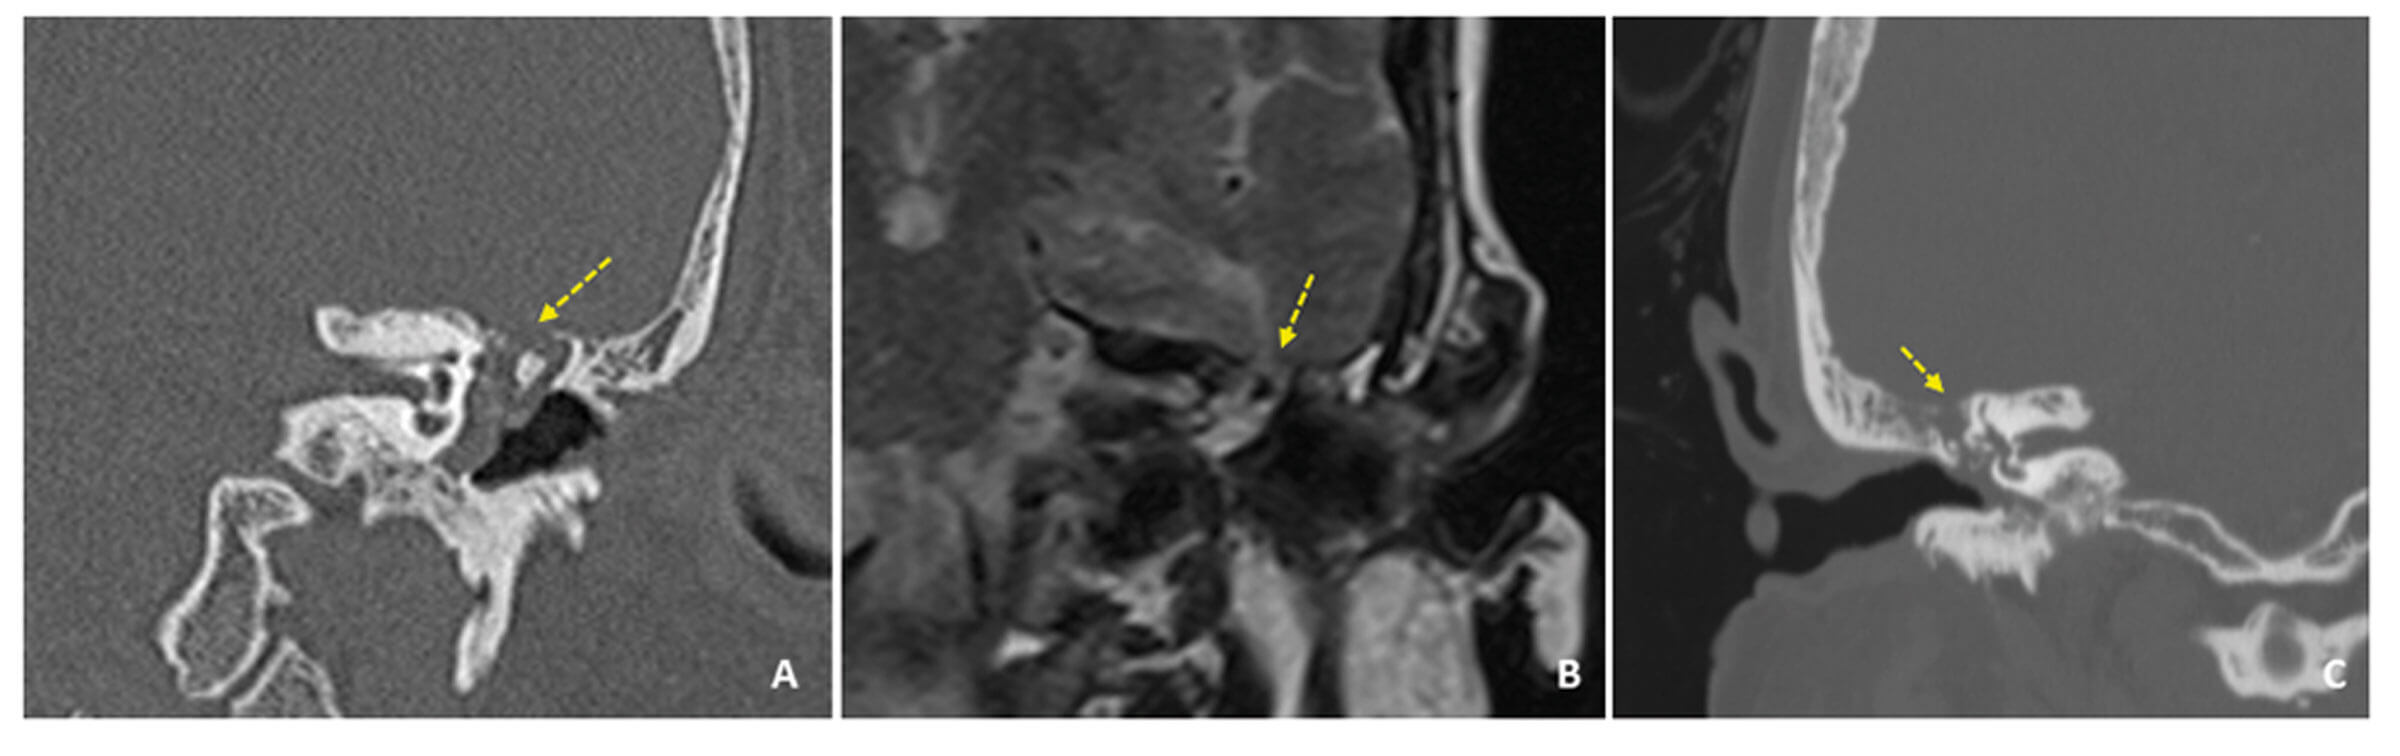

Non-absorbable synthetic material for middle fossa repair using a combined transmastoid/middle fossa approach

Repair of CSF leaks can be a challenging technical undertaking. In this article, the authors describe their use of a synthetic material to help with the successful repair of these leaks from the middle cranial fossa. Erosion of the middle...